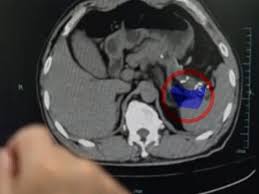

“फैटी लीवर (स्टीटोसिस) तब होता है जब लीवर की कोशिकाओं के आसपास वसा जमा हो जाती है, और वसा को तोड़ने की प्रक्रिया धीमी हो जाती है। यह स्थिति अक्सर अपने लक्षणहीन स्वभाव के कारण किसी का ध्यान नहीं जाती है,” डॉ. मल्लिकार्जुन सकपाल, कंसल्टेंट, एचपीबी और ट्रांसप्लांट फिजिशियन, एस्टर सीएमआई अस्पताल, बैंगलोर ने जोर दिया।

इस प्रकार, वसा के चयापचय के लिए जिम्मेदार यह महत्वपूर्ण अंग “कमजोर हो जाता है और अधिक बोझिल हो जाता है। इससे आगे चलकर सूजन (स्टीटोहेपेटाइटिस), निशान (फाइब्रोसिस) और सिरोसिस या लीवर कैंसर जैसी संभावित गंभीर जटिलताएँ हो सकती हैं,”।